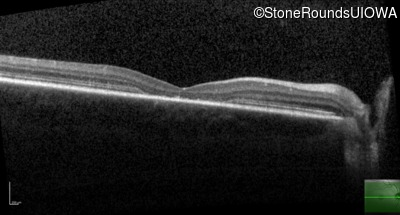

Age at visit: 15 years

Age at visit: 16 years